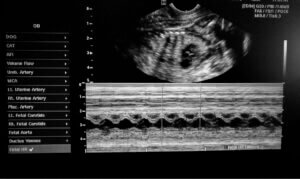

Nous avons affaire à une entité clinique exceptionnellement rare. Il est donc très difficile d’avoir suffisamment d’informations pour élucider une cause claire et uniforme. De manière générale, on pense que des échecs génétiques et l’ingestion d’agents toxiques par la mère pendant la grossesse favorisent la cyclopie.

Selon le vétérinaire qui a traité Cyclope, la chienne a probablement ingéré des éléments toxiques avant de donner naissance au chiot en question. Elle était par ailleurs âgée, de sorte que sa capacité fertile avait naturellement diminué. Tous ces facteurs, pris ensemble, ont conduire à cet événement.